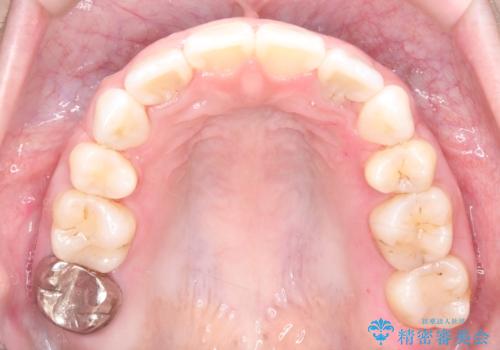

1年半の治療期間を経て、抜歯したスペースは完全に閉じ、突き出ていた前歯はすっきりと内側に収まりました。噛み合わせの精度も向上し、機能面でも良好な結果が得られています。

治療完了後、口元の突出感が解消されたことでお顔全体の印象がシャープになり、患者様からも大変満足していただくことができました。目立ちにくい装置を使用したことで、1年半という期間も無理なく継続し、理想的なゴールを迎えることができました。